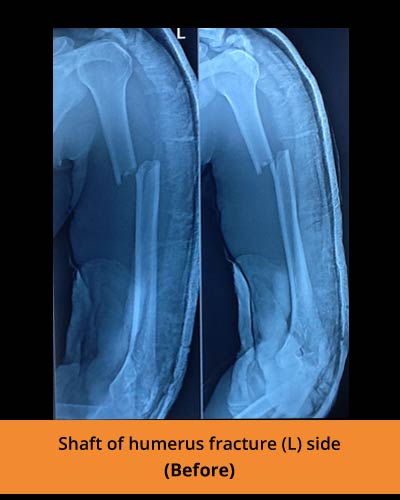

🩺 Fracture management and trauma care

At TPN Hospitals — the top orthopaedic hospital in Erode — our specialists use advanced methods to perform limb lengthening, correct deformities, and treat complex fractures with precision and care

Addressing infected non-union of long bones, osteomyelitis, and polytrauma cases with specialized care.